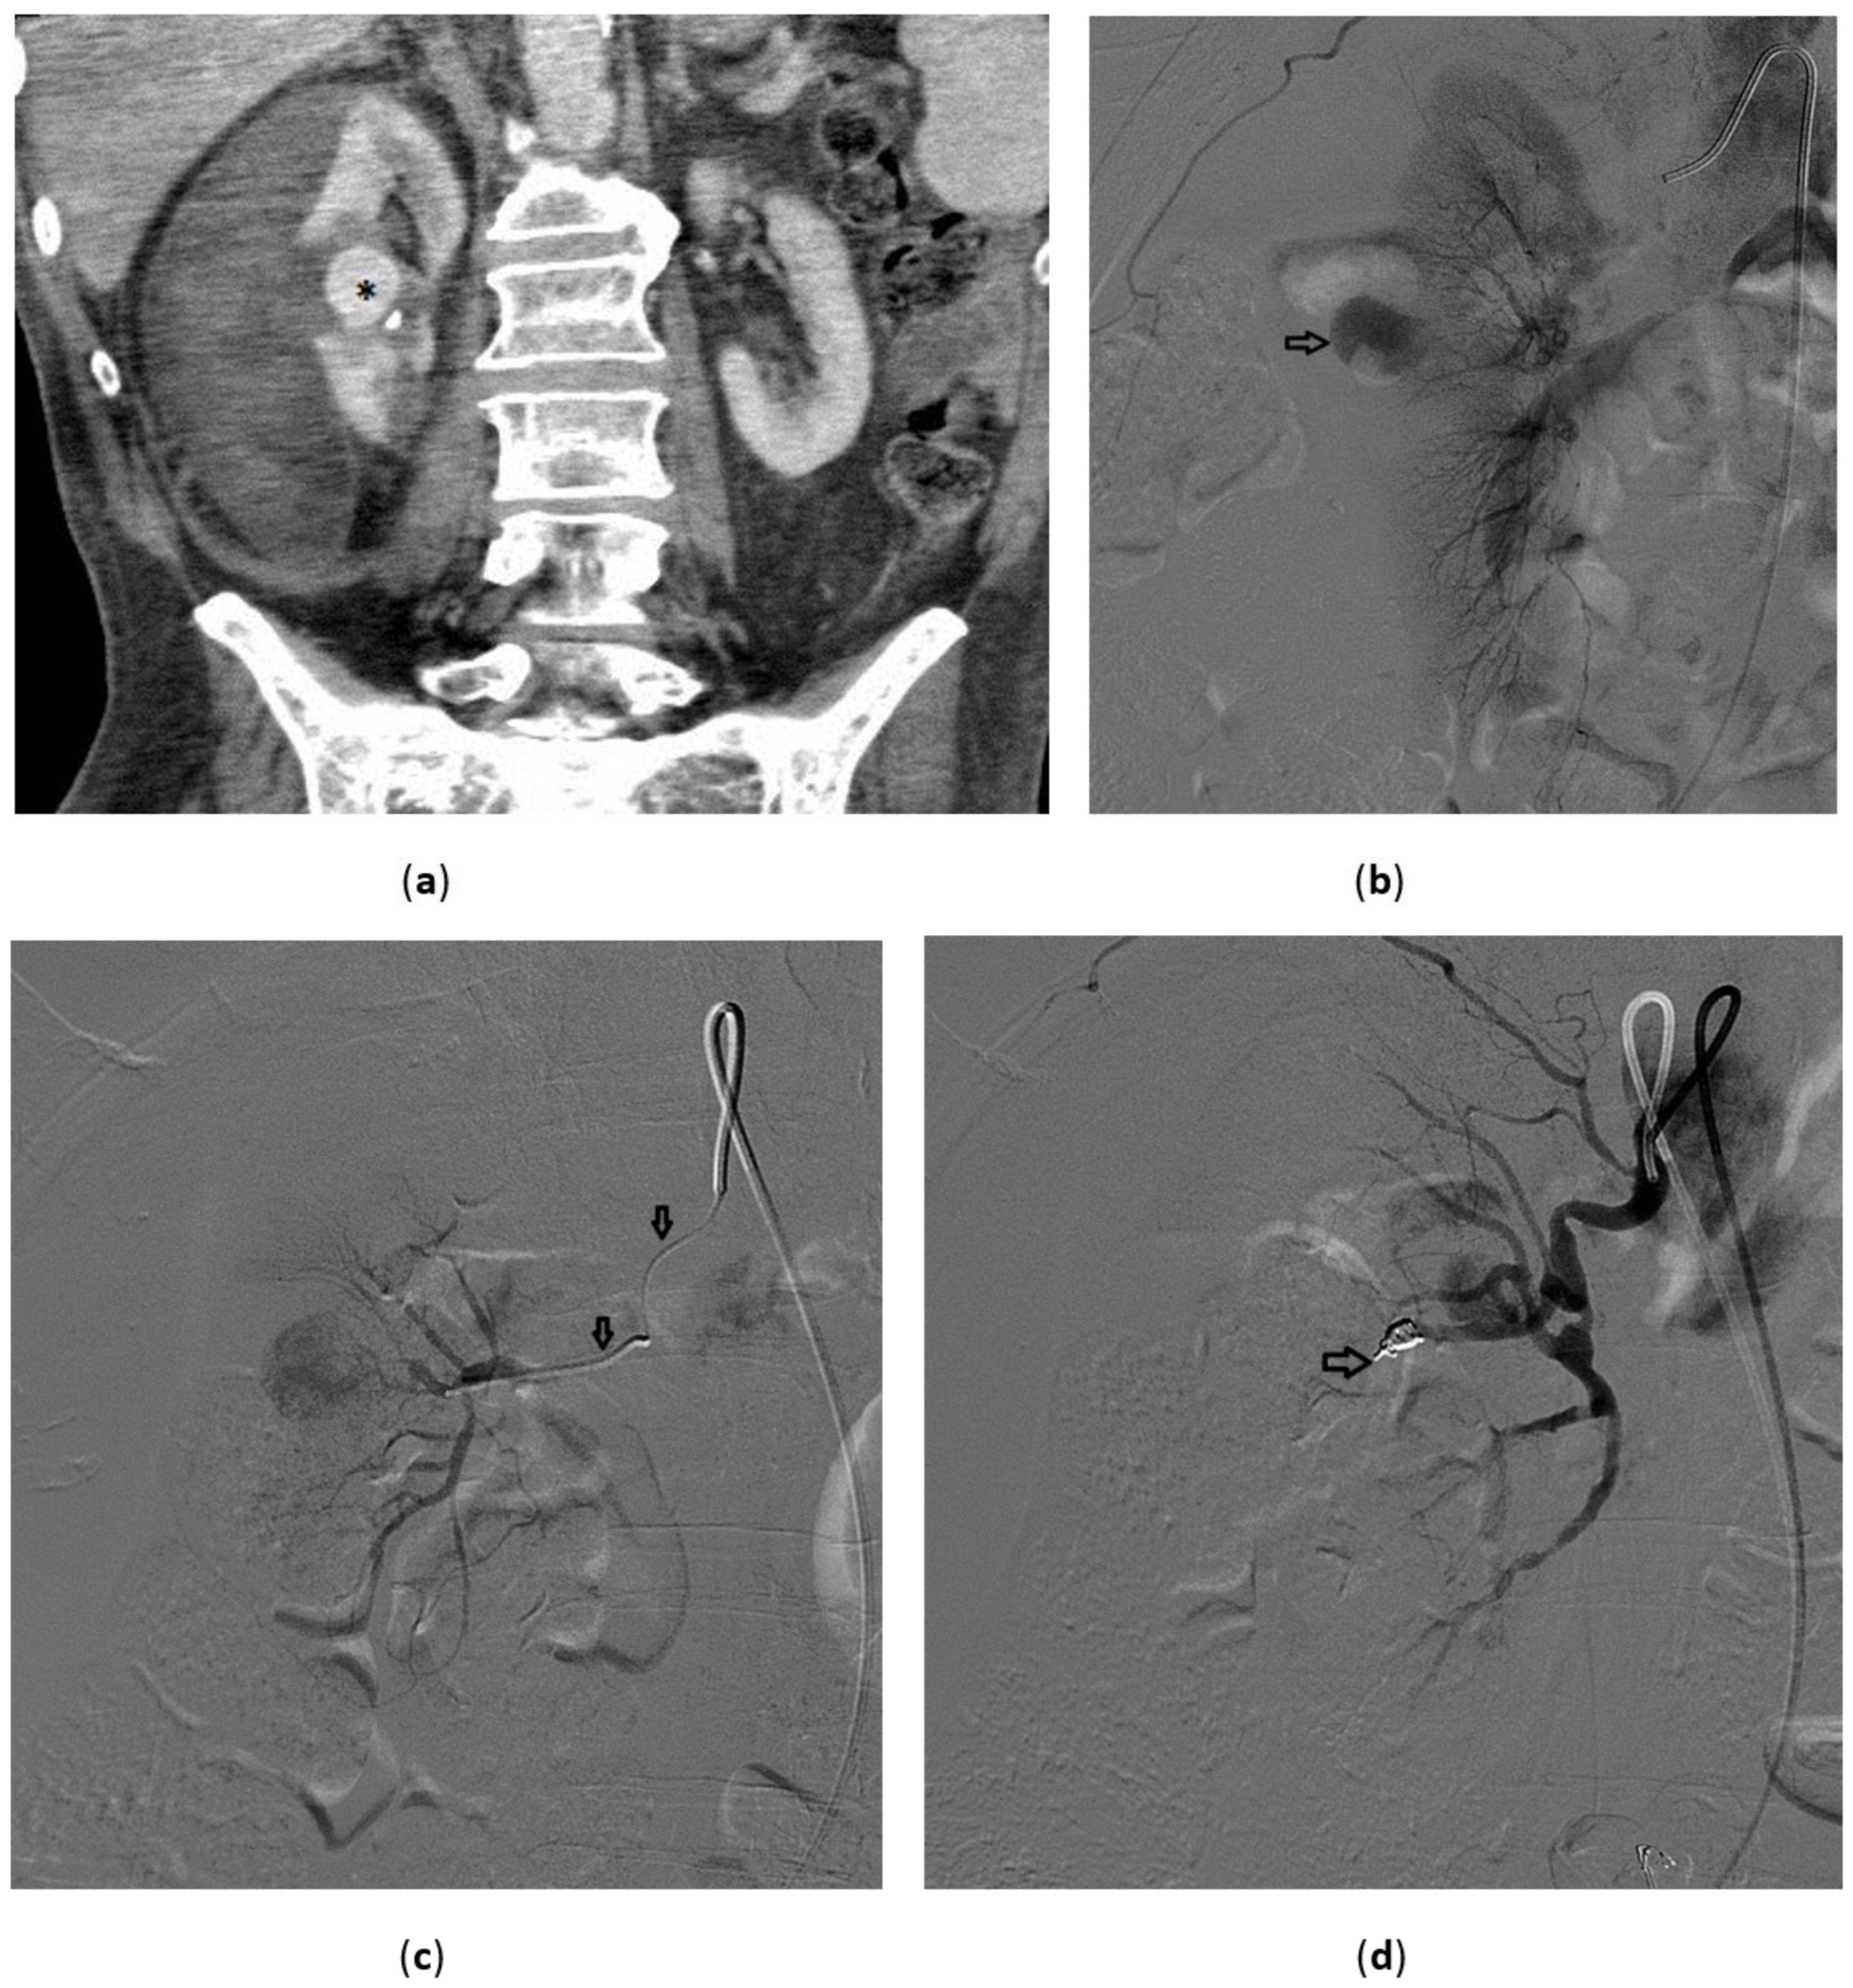

3.5. Renal Angiomyolipoma

3.6. Malignant Renal Tumors